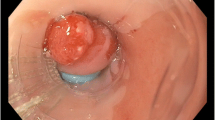

4.13 Patient Selection and Technical Considerations

Patients referred for endoscopic therapy should have a detailed white light exam with a high-definition endoscope to identify landmarks and any visible abnormalities. Four quadrant surveillance biopsies should be performed every 1 cm along with endoscopic resection of suspicious areas. Diagnoses of dysplasia need to be confirmed by an expert gastrointestinal pathologist. In cases of HGD and intramucosal cancer with low risk of lymph node metastases such as lesion size less than 2 cm, well-differentiated histology, and absence of lymphovascular invasion, endoscopic therapy is preferred over esophagectomy. After EMR of visible lesions, residual Barrett’s needs to be ablated in view of high risk of metachronous neoplasia. In the absence of visible lesions, ablative therapy is the treatment of choice. In view of risk of recurrence, patients need to be on ongoing surveillance with treatment of recurrences endoscopically.

Due to the lack of head-to-head randomized controlled trials comparing different ablative therapies, no one ablation modality suits all patients. A comparison of different ablation techniques is presented in Table 4.1. In patients with long-segment Barrett’s where large surface areas need to be treated, RFA is the treatment modality of choice. Other options include PDT and cryotherapy. For small areas of residual Barrett’s, APC and MPEC may be cost-effective modalities. For patients with nodular disease where close apposition with RFA is not possible, options are cryotherapy, PDT, and stepwise radical EMR. In patients with persistent areas of Barrett’s in spite of repeated ablation, EMR can be used.